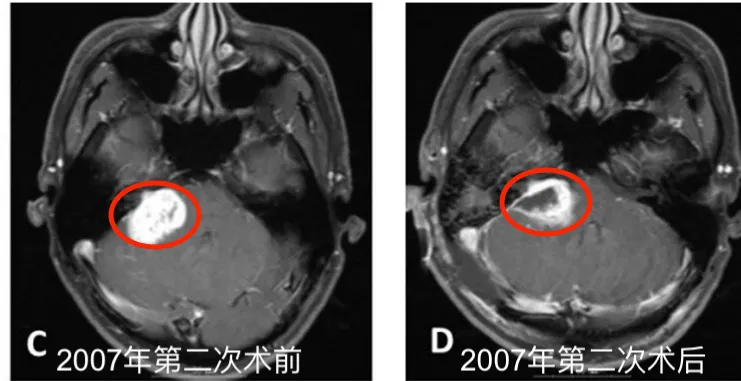

2004年5月,患者确诊为听神经瘤并接受首次开颅手术。术后病理检查确认诊断,初期治疗显示右侧桥小脑角区肿瘤呈现不均匀强化表现。为控制术后残留病灶,2005年8月实施伽玛刀治疗。2007年5月随访发现肿瘤再次进展,遂行第二次开颅手术。

2004年4月初始MRI显示右侧桥小脑角区肿瘤不均匀强化。2005年8月首次术后、伽玛刀治疗前影像资料记录肿瘤状态。2007年5月第二次术前MRI评估显示肿瘤进展,术后一个月影像确认切除范围。